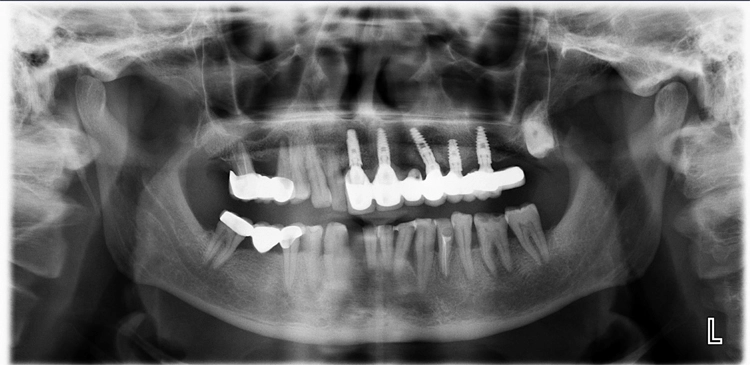

Falls gewünscht, können die maschinell detektierten Befunde vom Behandler angepasst oder ergänzt werden. Anschließend stehen Befund und Therapieempfehlung für das Patientengespräch bereit. Da dentalXrai die Detektion farblich hervorhebt, ist sie auch für den Patienten am iPad verständlich und nachvollziehbar (Abb. 3–6). Ein automatisch erstelltes Gesprächsprotokoll mit der dentalXrai-Befundung kann dem Patienten ganz einfach per verschlüsselter Mail geschickt werden.

dentalXraiAbb. 3–6: Der Vergleich von nativem Röntgenbild (am Beispiel von OPG und Bissflügelaufnahme verschiedener Patienten) und dem Bild mit eingeblendeten Detektionen zeigt die Gründlichkeit der KI-Befundung. Die befundeten apikalen Läsionen sind orangefarben markiert, die Karies rot. Bestehende Versorgungen sind blau und türkis hervorgehoben. Die Zahnsituation ist so für den Patienten im Gespräch gut nachvollziehbar und auch in der Nachbereitung zuhause immer wieder gut zu erkennen.